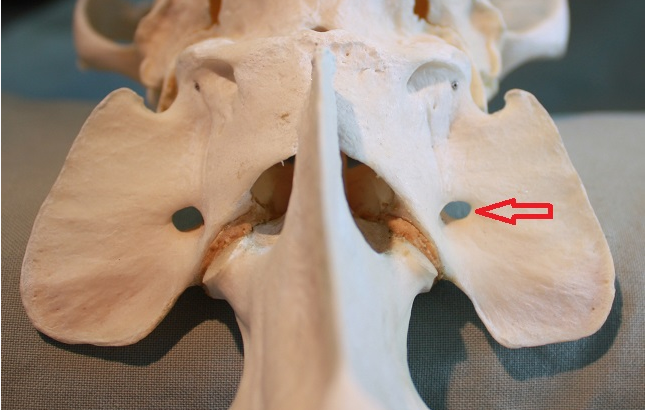

Site of insertion for the sacrotuberous ligament

Red arrow- 4th tarsal bone